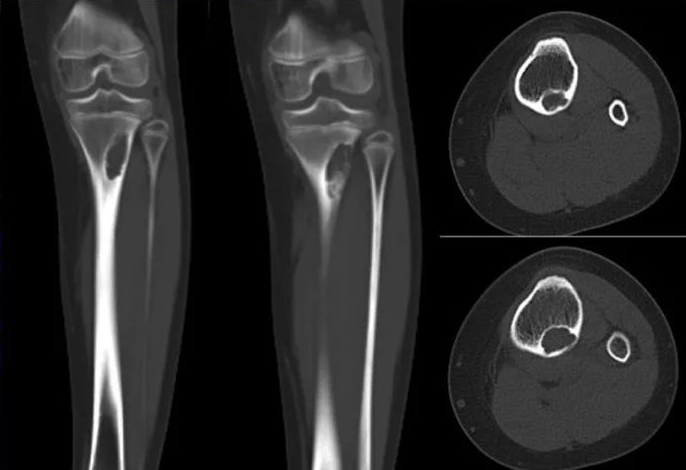

②非骨化性纤维瘤:多发生于长骨骨皮质内或骨皮质下,为多囊状、分叶状软组织密度,周围可见较厚硬化环。

注:9 岁女孩,左侧胫骨近端干骺端 NOF。胫骨近端干骺端徧心性溶骨性病变, 以后缘皮质为基底突向髓腔,浅分叶状,边缘清晰锐利硬化。